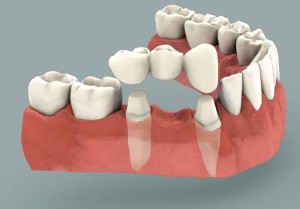

Doğal dişlerden destek alınarak, yapılan bir takım hazırlıklardan sonra, destek dişlerin üzerine yapıştırılıp sabitlenerek kullanılan protezlere denir. Eksik bölgeye komşu, yeterli sayıdaki destek dişin frezlerle preparasyonu (aşındırılması) sonrasında ölçü alınarak laboratuvar ortamında sabit protezler hazırlanır. Sabit protezler ya da porselen kuron ve köprüler de kendi arasında sınıflandırılabilir:

- Metal altyapılı kuron ve köprüler

- Zirkonyum altyapılı kuron ve köprüler

- Metalsiz kuron ve köprüler (full porselen kuronlar, porselen laminalar vb.)